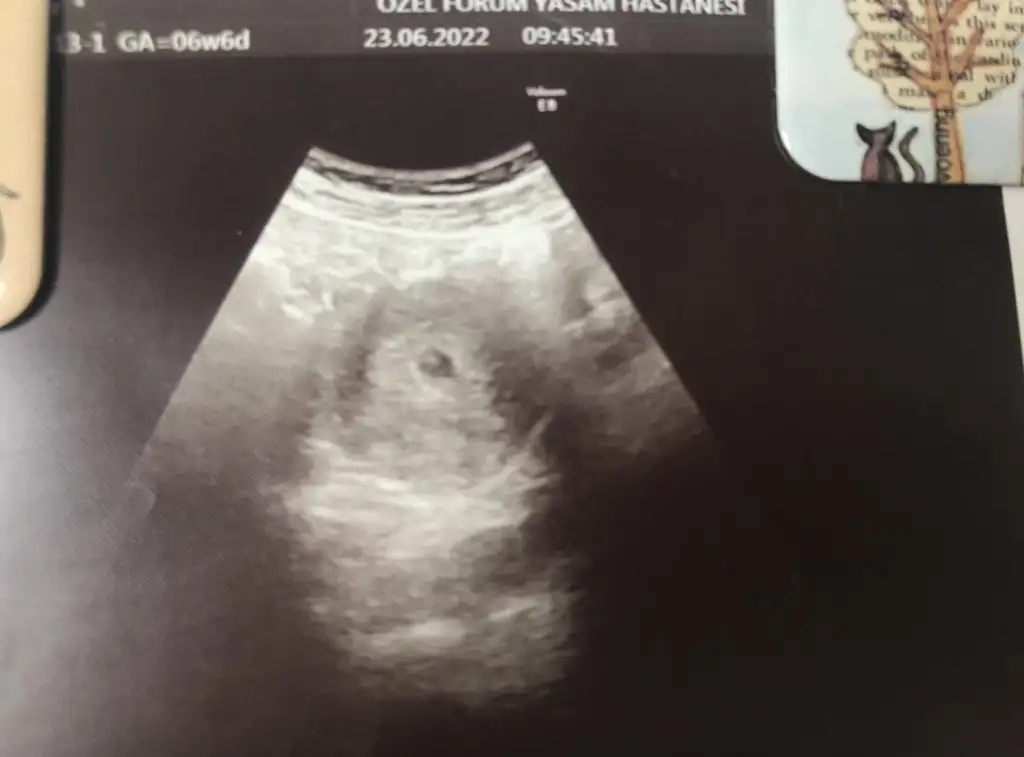

Kuzum buda sana Rabbim in mucizesiKızlar merhaba yeni katıldım ben. 5 düşük yaptım 1 aşılama 2 tüp bebek tutmadı onlarda. Son reglim 6 Haziran da bitti bittiğinde ilişki oldu 3/2 arayla yapmaya devam ettik geçen hafta göğüs hassasiyeti oluştu bende bu hafta da idrar sık çıktım mide rahatsızlığı kabızlık ve baş dçnöeleri başladı naBzımı ölçtüm 86 çıktı normalde 70/75 arası çıkardı erken ama yine de idrar testi yaptım çift çizgi çıktı dün akşam üzeri kan verdim 234 çıktı daha adetime 7 gün var. Nasıl oldu anlamadım böyle olan oldu mu kızlar hiç

Adet bititği zaman mı acaba tuttu bilmiyorum ki daha adetime 1 hafta varken değerim 234 çıktı yüksek gibi geldi bütün belirtileri yaşıyorum bilmiyorum korkuyorum aslında sürekli kalp atışına kadar gelmiştim ama normal yollarla gebe kalamıyordum dr un bitkisel vitaminleri çok etkiledi demekki dr MFK ürünleri kullandıktan sonra gebe kaldım. Yoksa bayramdan sonra tüp bebek yaptıracaktık olmuyor diye. İnşallah bu sefer tutunur kızlar. Yaş 35 çok yorulduk çok tükendik eşimde bende sürekli tedavilerden geçtim. Bu gerçekten mucize oldu bizim içinKuzum buda sana Rabbim in mucizesiinsallah saglikla alirsin kucagina, erken döllenme olmus büyük ihtimal. Bizide haberdar et durumundan lutfen

İnsallah saglikla kucagina alirsin. Sana iki şey soylicem adetime 6 gün kala seneler önce testler bile küçük hcg yi anlayamazken ben gebeligimi ogrenmistim kaset testle. Adet gunumde ise yuksek cikmisti hcg hatta doktor ikiz gebelik olabilir demisti keseyi goremeyince ve kızım suan 8 yasinda ayrica erken dogum oldu ama kilosu boyu iyiydi.. Bide bunuda yeni ogrendim maalesef bi arkadaşımızdan boş gebelik olabilir yuksek cikan hcg diyordu. İnsallah senin sonun benimki gibi olur guzel saglikli bi evlatAdet bititği zaman mı acaba tuttu bilmiyorum ki daha adetime 1 hafta varken değerim 234 çıktı yüksek gibi geldi bütün belirtileri yaşıyorum bilmiyorum korkuyorum aslında sürekli kalp atışına kadar gelmiştim ama normal yollarla gebe kalamıyordum dr un bitkisel vitaminleri çok etkiledi demekki dr MFK ürünleri kullandıktan sonra gebe kaldım. Yoksa bayramdan sonra tüp bebek yaptıracaktık olmuyor diye. İnşallah bu sefer tutunur kızlar. Yaş 35 çok yorulduk çok tükendik eşimde bende sürekli tedavilerden geçtim. Bu gerçekten mucize oldu bizim için

İşte bende dış gebelikten korktum ama hiç dış gebelik yaşamadım 11 yaşında kızım var 7 yıldır yapıyoruz çocuk 5 defa düşük oldu sonrada gebe kalamadım tüp benek aşılama vs. Derken bu sefer kendiliğinden kaldım. Değerim yüksek çıktı ikiz olabilirde dediler. Mesela Benim ikiz kardeşim var kaynpederimin de ikiz kardeşi var genlerde de var ikiz çocuk. Bilmiyorum yerın test yaptıracağım artıysa 1 hafta bekleyip doktora gideceğim. Keseyi görmek için aksilik Cumartesi tatile gidiyorum herşeyi ayarlamıştık daha nisan ayında. Neyse bol bol dinlenirim artık. Döndüğüm zaman doktora gözükürüm inşallah her şey normal ilerlerİnsallah saglikla kucagina alirsin. Sana iki şey soylicem adetime 6 gün kala seneler önce testler bile küçük hcg yi anlayamazken ben gebeligimi ogrenmistim kaset testle. Adet gunumde ise yuksek cikmisti hcg hatta doktor ikiz gebelik olabilir demisti keseyi goremeyince ve kızım suan 8 yasinda ayrica erken dogum oldu ama kilosu boyu iyiydi.. Bide bunuda yeni ogrendim maalesef bi arkadaşımızdan boş gebelik olabilir yuksek cikan hcg diyordu. İnsallah senin sonun benimki gibi olur guzel saglikli bi evlat